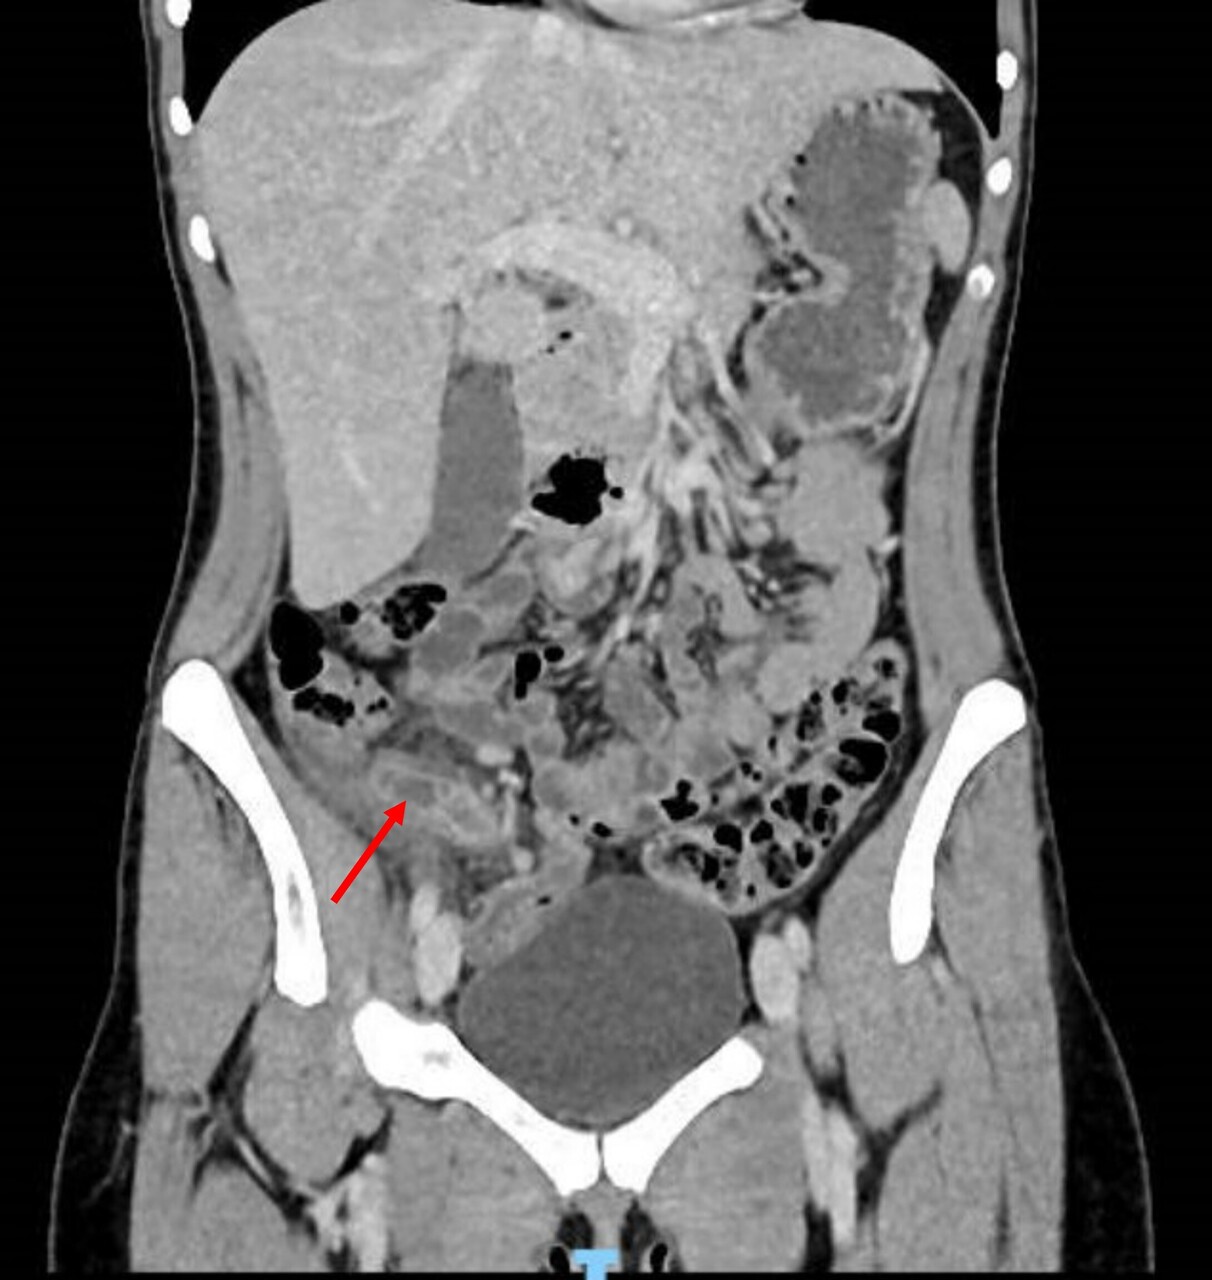

Avant l’ère des explorations radiologiques, la triade fièvre-défense en fosse iliaque droite-hyperleucocytose poussait à l’indication chirurgicale, avec un taux non négligeable (jusqu’à 25 %) d’appendicectomies effectuées sur un appendice sain. La réalisation systématique d’une imagerie abdominale a permis de diminuer significativement le taux d’appendicectomies inutiles. Les recommandations émises par les Sociétés françaises de chirurgie digestive et de radiologie préconisent donc la réalisation systématique d’une imagerie lors de la suspicion clinico-biologique d’appendicite aiguë (fig. 1).

Scanner abdominopelvien injecté : la référence

Le scanner abdominopelvien avec injection intraveineuse de produit de contraste est l’examen de référence, avec une excellente performance diagnostique. Il permet, dans le même temps, d’éliminer de nombreux diag­nostics différentiels et détermine la présence ou non d’une complication de l’appendicite, telle qu’un abcès ou une péritonite. Le diagnostic ­positif repose sur une augmentation du diamètre de l’appendice, une infiltration de la graisse périappendiculaire, un épaississement et une prise de contraste de ses parois (fig. 2).